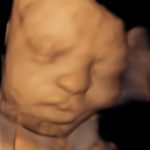

4D/5D/HD Ultrasound Gallery

Gallery